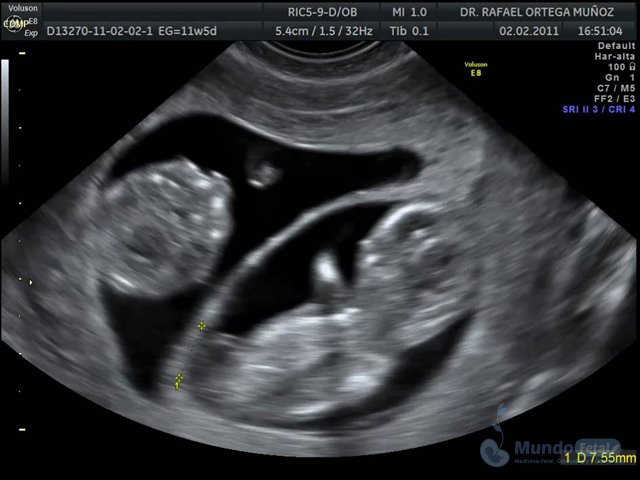

Es esencial detectarlo desde el primer trimestre (especialmente 11-13.6 semanas de gestación) con la intención de conocer el número de bebes, cuántas placentas y bolsas amnióticas, ya que el seguimiento de estos es distinto, esto por los riesgos que conllevan de presentar alguna alteración propia de estos embarazos, indicativos de una vigilancia estrecha y estudios complementarios, durante toda la gestación.

• Valorar el bienestar de los bebes, de acuerdo a su evolución en relación al tipo de embarazo.

• Descartar o confirmar oportunamente riesgos y anomalías, sugerentes de vigilancia y estudios complementarios.